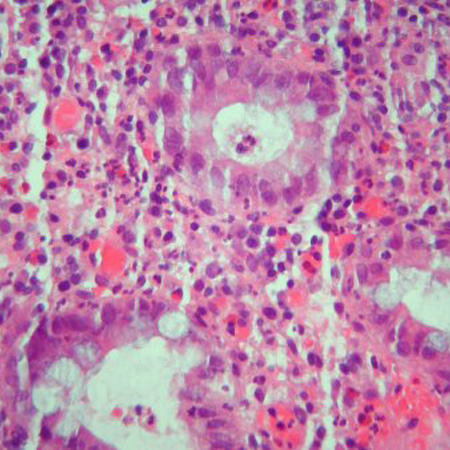

Deben obtenerse biopsias colónicas e ileales segmentarias para evaluar la evidencia microscópica de enfermedad de Crohn (EC).[70] Las características microscópicas que ayudan a distinguir la colitis ulcerosa y la EC son los granulomas, los cambios arquitectónicos y la distribución de la enfermedad.[81] Sin embargo, la inflamación granulomatosa se registra en una minoría de pacientes con EC (del 30% al 50%); no es necesaria para el diagnóstico.[71][81][Figure caption and citation for the preceding image starts]: Inflamación significativa de la pared del colon, engrosamiento de la submucosa y acumulaciones linfoides densas en la submucosaProporcionado por los doctores Wissam Bleibel, Bishal Mainali, Chandrashekhar Thukral, y Mark A. Peppercorn, los anteriores autores de este tema [Citation ends].

[Figure caption and citation for the preceding image starts]: Granulomas en un paciente con la enfermedad de Crohn; observe la acumulación de histiocitos epitelioidesProporcionado por los doctores Wissam Bleibel, Bishal Mainali, Chandrashekhar Thukral, y Mark A. Peppercorn, los anteriores autores de este tema [Citation ends].